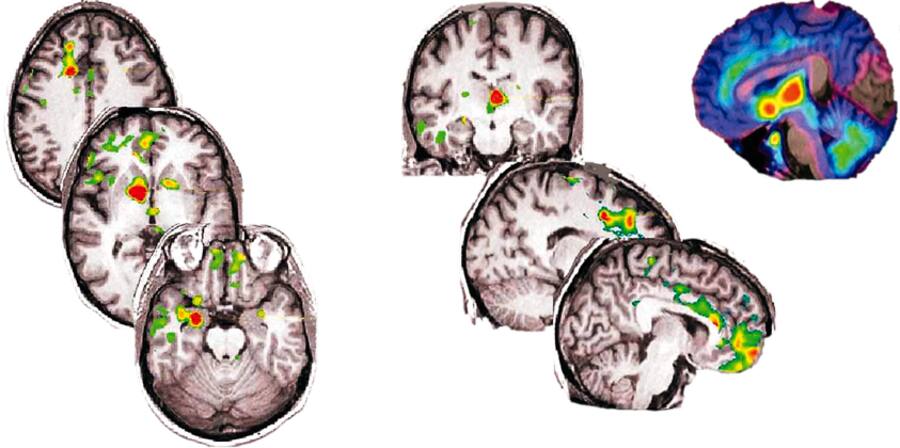

Diesen Umstand machte sich Placebo-Forscher Jon-Kar Zubieta von der University of Michigan zunutze. Er erzeugte bei 14 gesunden Freiwilligen Schmerzen, indem er ihnen eine Kochsalzlösung in die Kiefermuskeln injizierte. Dann verabreichte er eine Spritze mit angeblich schmerzlindernder Wirkung. Bald vermeldeten die Probanden ein Nachlassen ihrer Schmerzen. Gleichzeitig liessen die PET-Bilder erkennen, dass in bestimmten Regionen ihres Gehirns Endorphin-Bindungsstellen aktiviert wurden (siehe nachfolgende Grafik). Die hirneigene Schmerzabwehr war in Aktion getreten. «Dies versetzt der Idee, dass der Placebo-Effekt ein rein psychologisches statt physikalisches Phänomen sei, einen weiteren schweren Schlag. Die Verbindung zwischen Geist und Körper ist ziemlich klar», sagt Zubieta.

Mehr als nur psychologische Wirkung: Die Bilder oben zeigen Hirnareale während Schmerzerfahrung. Unten nach Verabreichung eines Placebos: Farbige Flächen zeigen Regionen, in denen das Gehirn selbständig schmerzunterdrückende Stoffe ausschüttete.

Quelle: University of Michigan